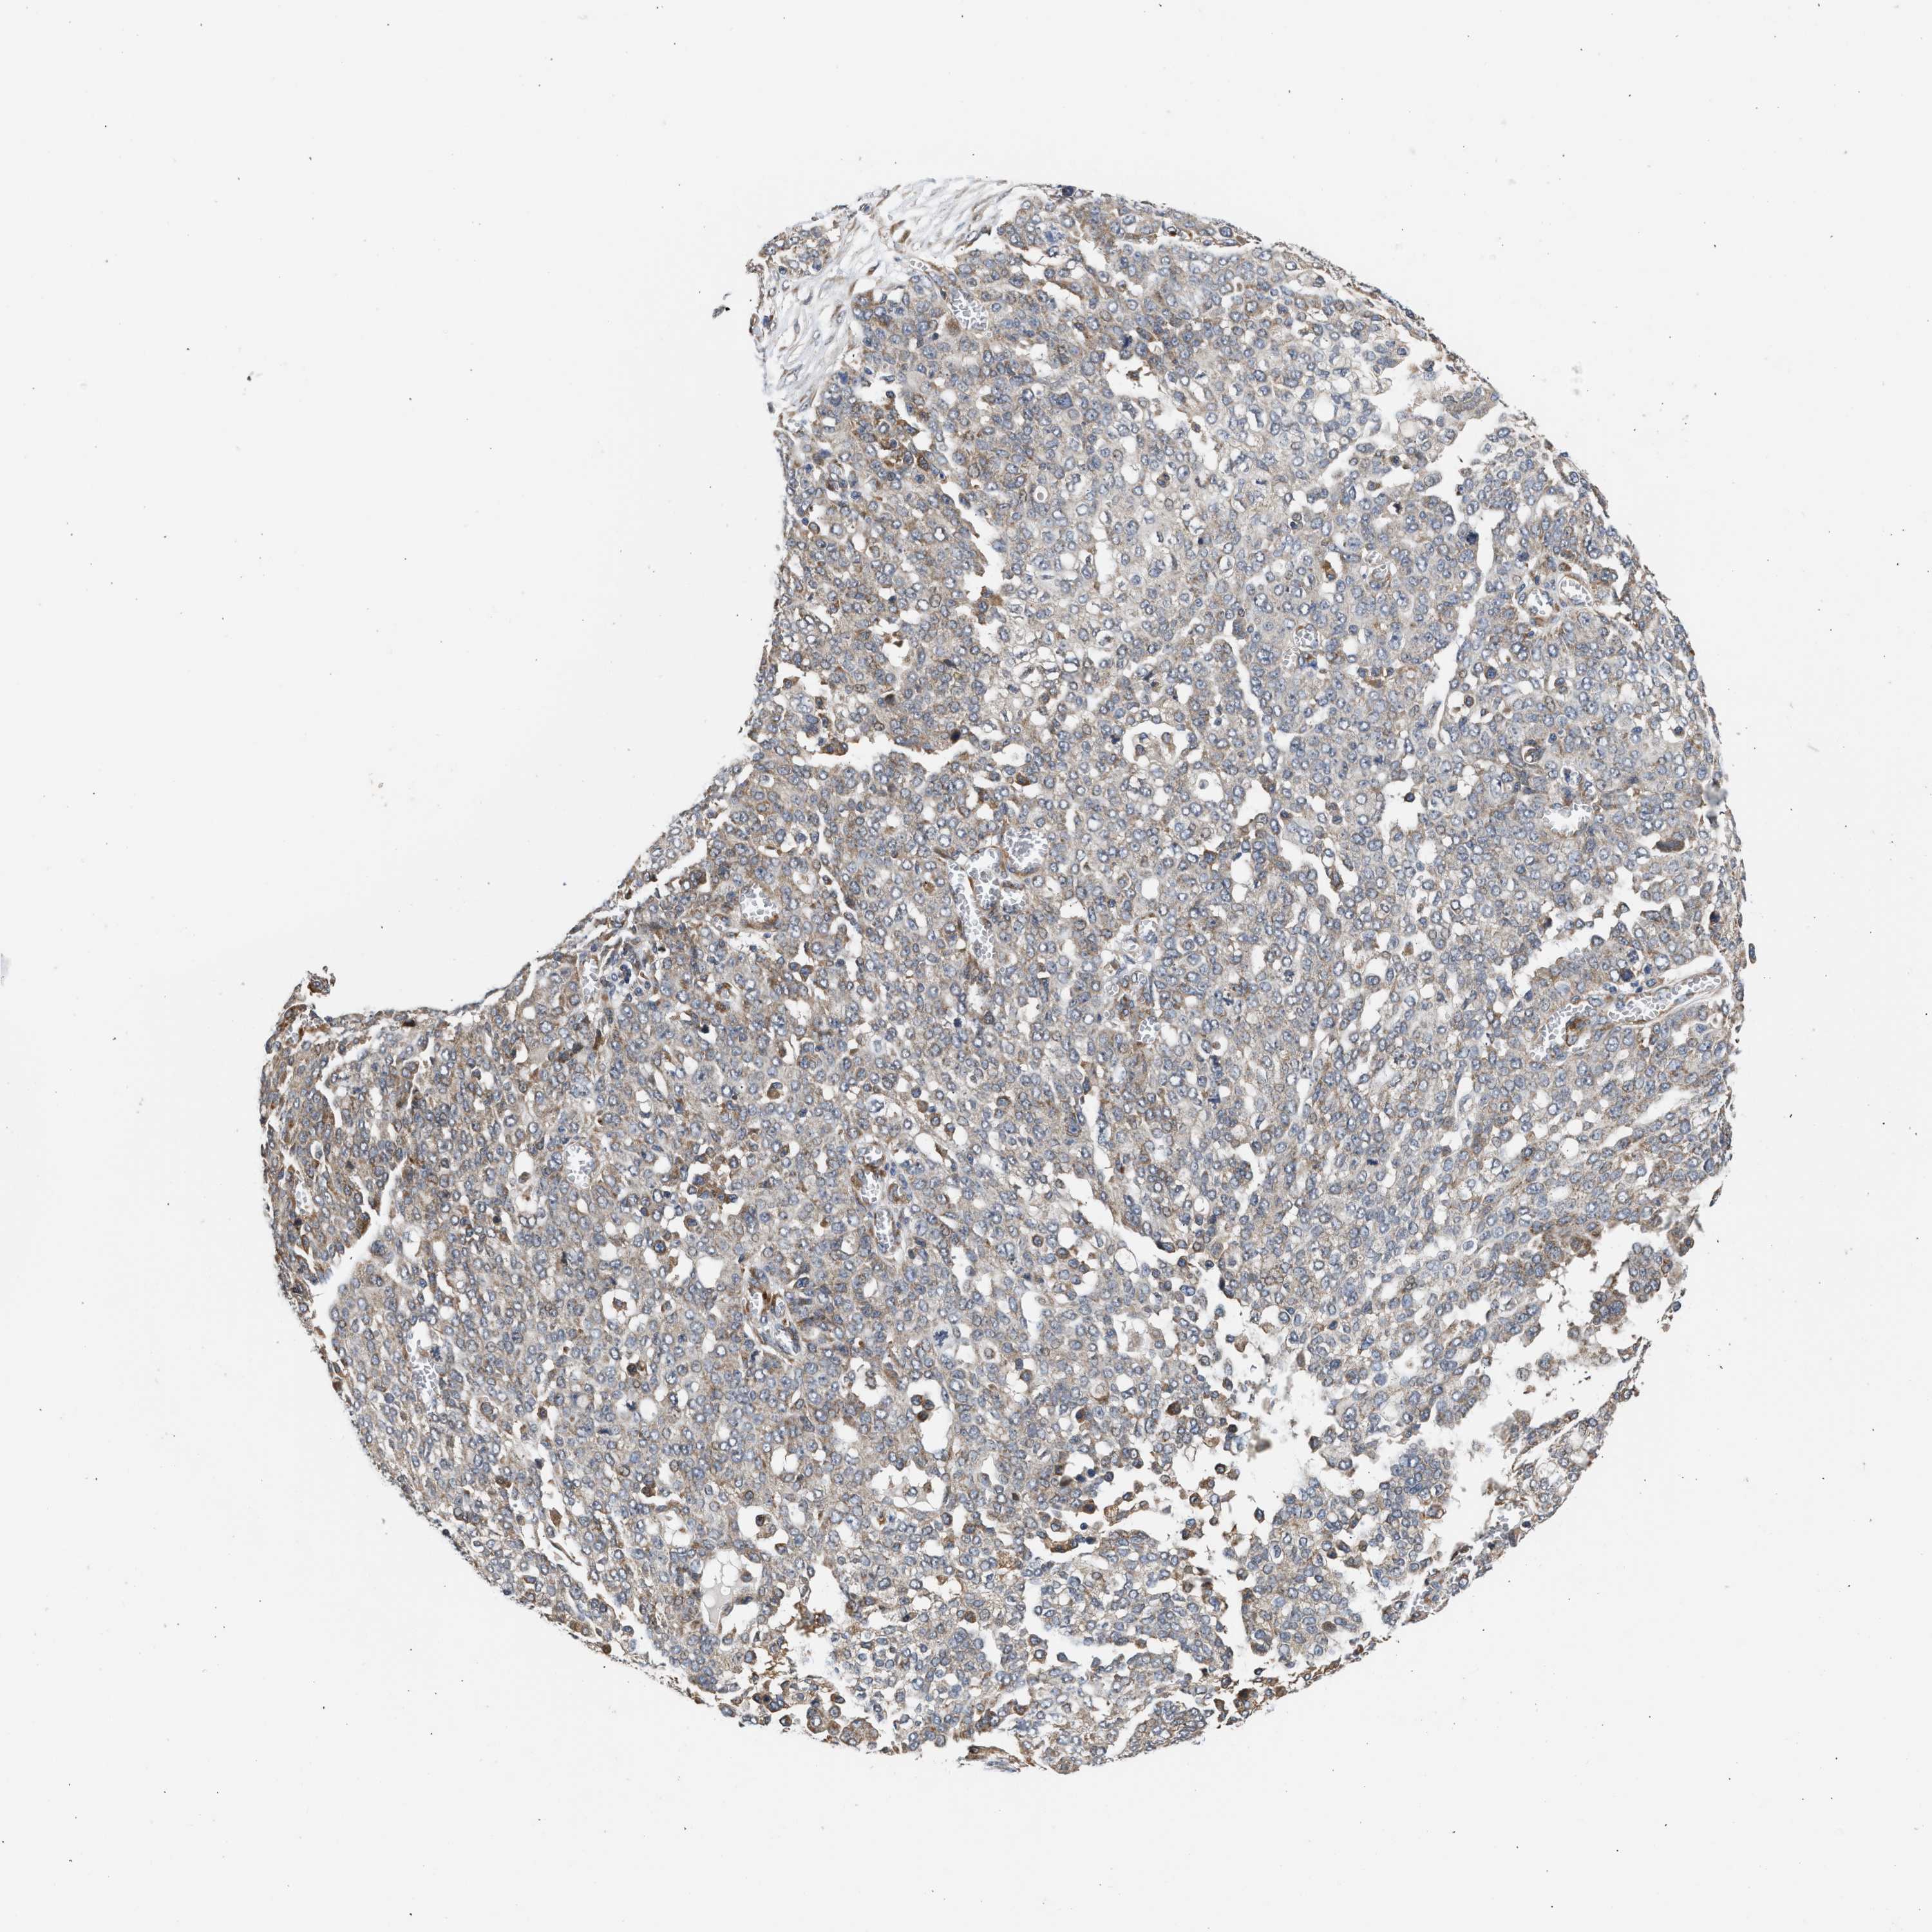

OVARIAN CANCER - Protein expressioni

A mouse-over function shows sample information and annotation data. Click on an image to view it in a full screen mode. Samples can be filtered based on level of antibody staining by selecting one or several of the following categories: high, medium, low and not detected. The assay and annotation is described here.

Note that samples used for immunohistochemistry by the Human Protein Atlas do not correspond to samples in the TCGA dataset.

Antibody stainingi

Antibody staining in the annotated cell types in the current human tissue is reported as not detected, low, medium, or high, based on conventional immunohistochemistry profiling in selected tissues. This score is based on the combination of the staining intensity and fraction of stained cells.

Each image is clickable and will lead to virtual microscopy that enables deeper exploration of all samples and also displays staining intensity scores, fraction scores and subcellular localization as well as patient and tissue information for each sample.

Antibody HPA023202

Antibody CAB017030

Cystadenocarcinoma, serous, NOS

Carcinoma, endometroid

Cystadenocarcinoma, mucinous, NOS

Carcinoma, NOS